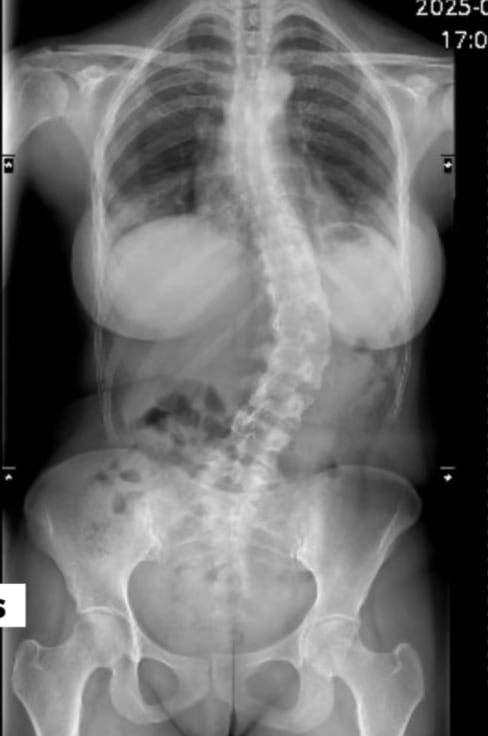

Ginnés Rodríguez

Ginnés Rodríguez está muy agradecida por las oraciones y las muestras de apoyo que le hacen llegar. (Tomada de redes sociales)